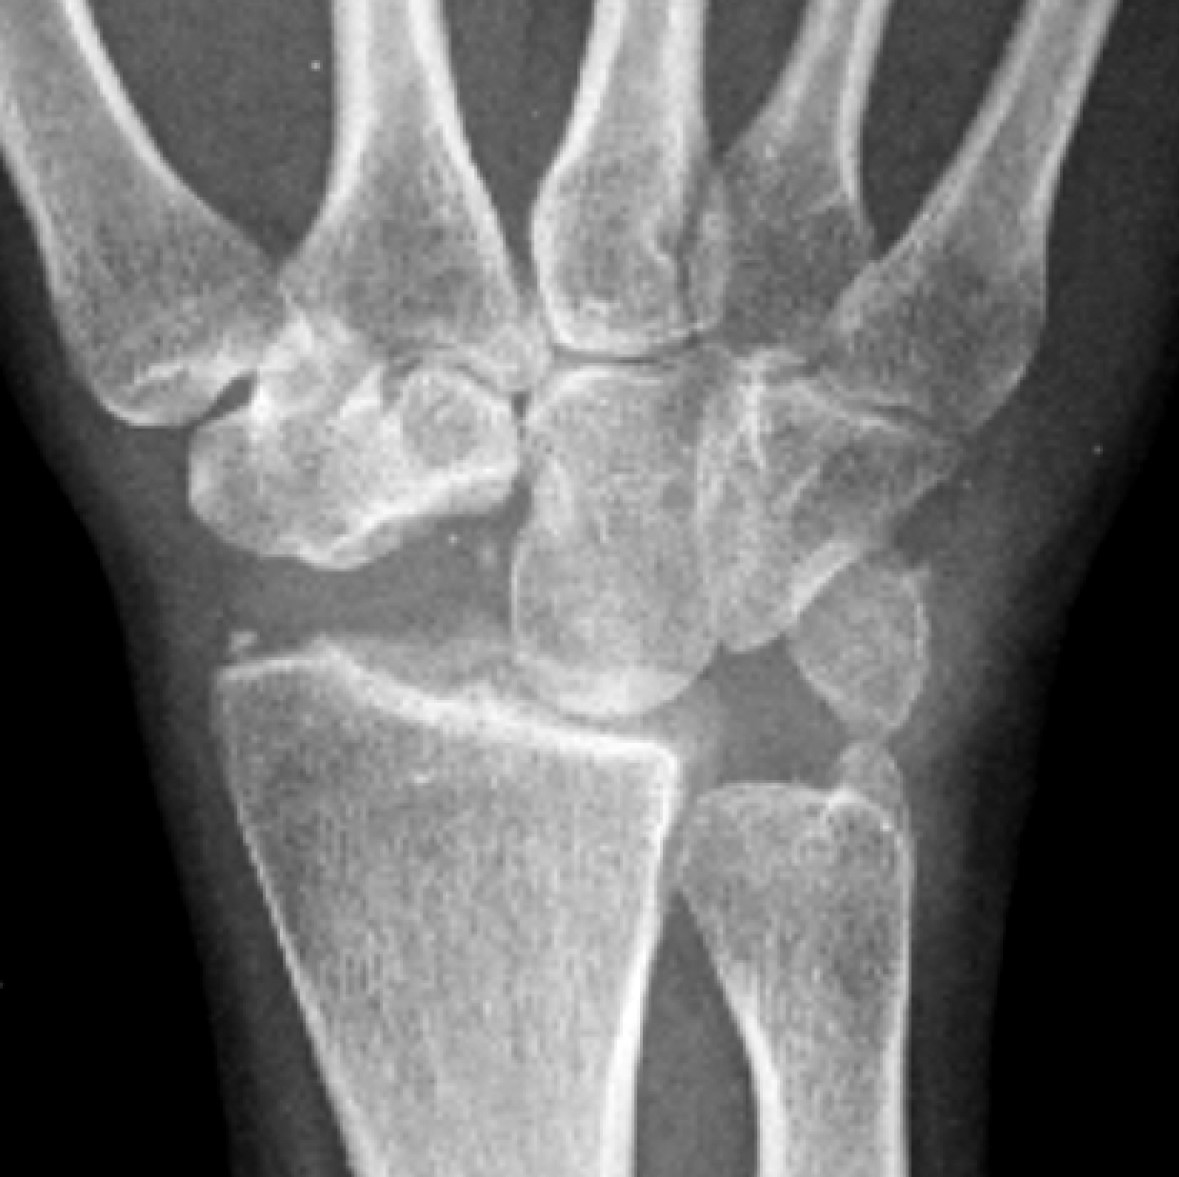

В течении SLAC выделяют три рентгенологические стадии [4, 23], по данным других авторов — четыре [24] (рис. 1).

Рис. 1. Фрагменты рентгенограмм кисти пациентов с разными стадиями SLAC в прямой проекции

Figure 1. X-ray fragments of patients´ wrists with various SLAC stages in the AP view

I стадия — поражены проксимальная часть ладьевидной кости и шиловидный отросток лучевой. На рентгенограммах в прямой проекции и на КТ на лучевой стороне ладьевидной кости и шиловидном отростке лучевой кости выявляются «острые подпорки» («клювы»), утрачивается нормальная округлая кривизна шиловидного отростка, развивается локальный артроз ладьевидной фасетки.

II стадия — поражение луче-ладьевидного сустава, прогрессивное сужение щели луче-ладьевидного сустава, склероз всей ладьевидной фасетки дистального луча.

III стадия — поражение головчато-полулунного сустава со склерозом и сужением суставной щели. При этом происходит проксимальная миграция головчатой кости со смещением полулунной кости в локтевую сторону.

IV стадия — дегенеративный артроз полулунно-лучевого сустава.